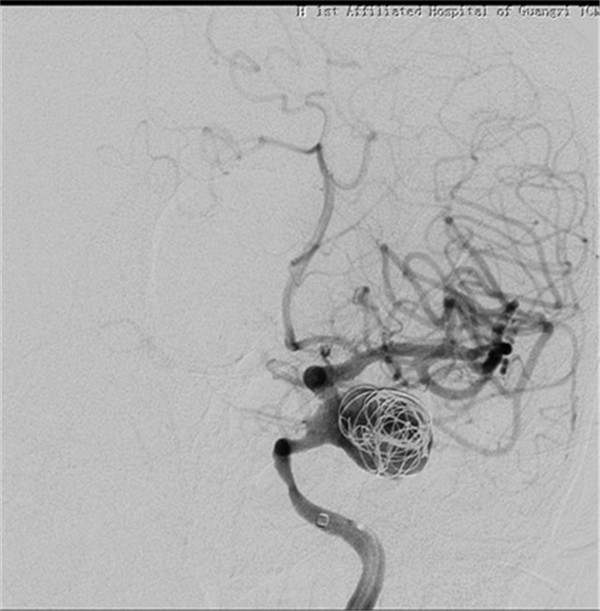

手术在气管插管全麻下进行,微导管顺利送到理想位置,由于出现血管痉挛,立即行解痉处理,好转后置入血流导向装置,由于瘤腔血流速度快,置入弹簧圈支撑支架,并缓慢释放装置,经造影显示动脉瘤消失,载瘤动脉通畅。手术过程顺利,术后患者神志清醒,言语切题,视力无异常改变,四肢活动正常,患者已缓慢下床活动,手术获得圆满成功。手术当日有来自广西区内多家医院神经外科主任的现场观摩与交流。

术后DSA